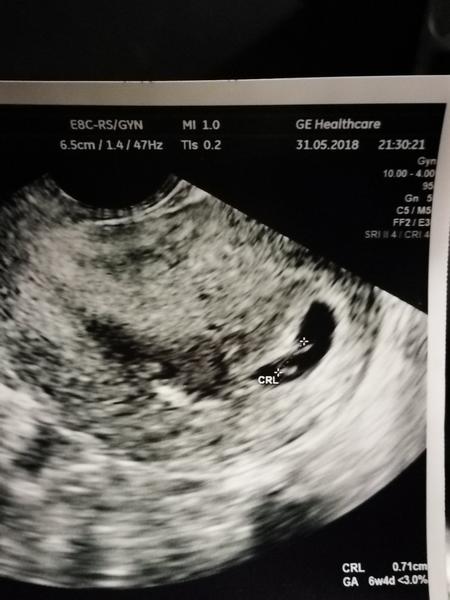

Po 5 tyzdni sa meria velkost gestacneho vaku/GSD/, od siesteho zltkoveho vaku/YS/ a neskor sa meria CRL velkost embrya od hlavicky po kostrc.. DO 12 tyzdna je najpresnejsie urcit podla CRL velkost plodu a to hlavne u zien, ktore maju nepravidelny cyklus a nevedia kedy cca ovulovali...To je najpresnejsie meranie a podla toho by sa malo riadit az do konca tehotenstva datum porodu..V druhom a tretom trimestri sa robia merania ako BPD, FL, HC,AC, ale uz sa nema upravovat termin porodu, pretoze v tychto tyzdnoch kazde dietatko rastie inak a su to len orientacne udaje na vypocet vahy babatka...Termin porodu ma byt vzdy stanoveny v prvom trimestri!

tak uz mame prvy obrazok fazulky 🙂